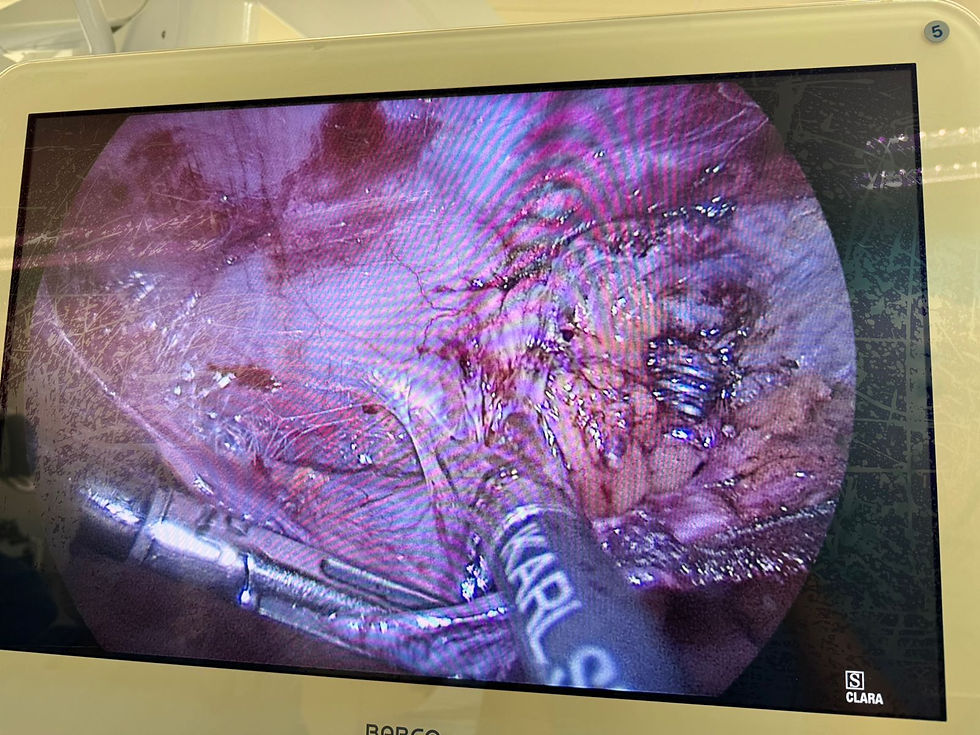

Nesse caso acima o paciente havia um excesso de tela e multiplas fixações com grampos o que aumenta o risco de dor! Após procedimento paciente ficou livre de dores após sofrer por mais de 2 anos com os sintomas!

Grampos encontrados na cirurgia

Múltiplas aderências